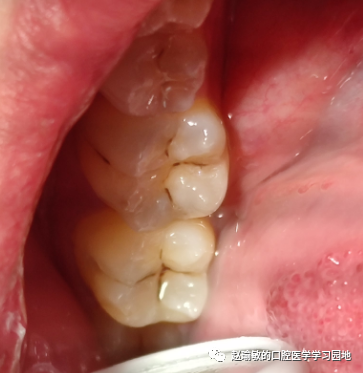

然后常规去龋,涂粘接剂,放树脂。然后把印章压到窝洞里。压之前应该在树脂和印章之间放个膜的,我没放,直接压了。然后把印章拿走,修形,光固化。还行,但是还是调了半天颌。这是第二个坑。

这就是我的一个简单的印章法树脂充填病例。第一次有很多缺憾,相信下一次会更好。补了7颗的,这只是其中一颗用了印章法的。